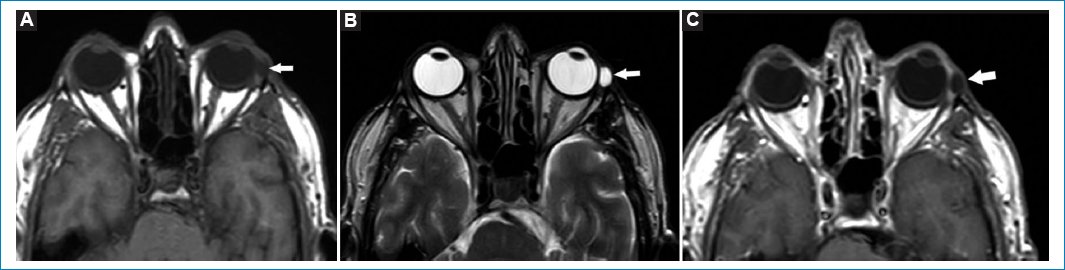

El adelgazamiento asociado a distensión de las membranas esclero-uveales, que como consecuencia genera un aumento de los diámetros anteroposteriores del globo ocular, se conoce como estafiloma24. El estafiloma puede ser unibilateral o bilateral y estar asociado a miopía del plano axial24,25. Se produce, entre otras causas, posterior a un traumatismo, radioterapia, cirugía, miopía o glaucoma24,25. Es bien apreciado en el plano axial en secuencias ponderadas en T2 (Fig. 6).

Figura 6. Imágenes potenciadas en T2. Cortes axiales en los que se evidencia elongación del diámetro antero-posterior de los globos oculares. Compatible con estafiloma (flechas).

La ptisis bulbi es la atrofia, asociada a calcificaciones, del globo ocular, secundaria a traumatismo o procesos infecciosos/inflamatorios previos26.

El globo ocular se aprecia heterogéneo, tanto en secuencias ponderadas en T1 como T2, con calcificaciones groseras asociadas. No es necesaria la administración de gadolinio (Fig. 7)27.

Figura 7. Imágenes potenciadas en T2. Cortes axiales. Se aprecia alteración y deformación del globo ocular, compatible con ptisis bulbi (flechas).

Los quistes simples dentro de las glándulas lagrimales son conocidos como dacriops28. Se producen por obstrucción de los conductillos glandulares. El antecedente de procesos infecciosos o traumatismos suele estar presente28. En TC se aprecian como masas hipodensas, mientras que en RM se ven hipointensos en T1 e hiperintensos en T2. Con contraste realzan periféricamente (Fig. 8)28.

Figura 8. Quiste de glándula lagrimal izquierda. Cortes axiales, secuencias: T1 (A), T2 (B) y T1 con gadolinio (C). Se aprecia (flechas) una formación quística, hipointensa en T1, hiperintensa en T2, realzando periféricamente con gadolinio, compatible con contenido líquido.